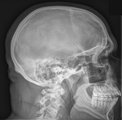

Wilhelm Conrad Röntgen